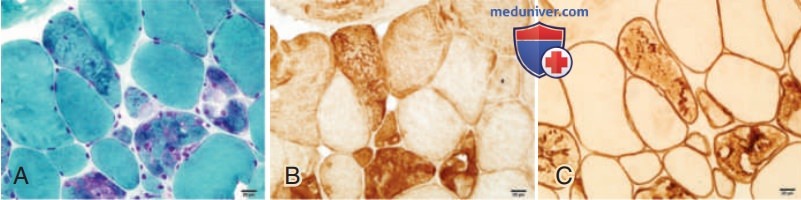

Дистрофия клетчатки